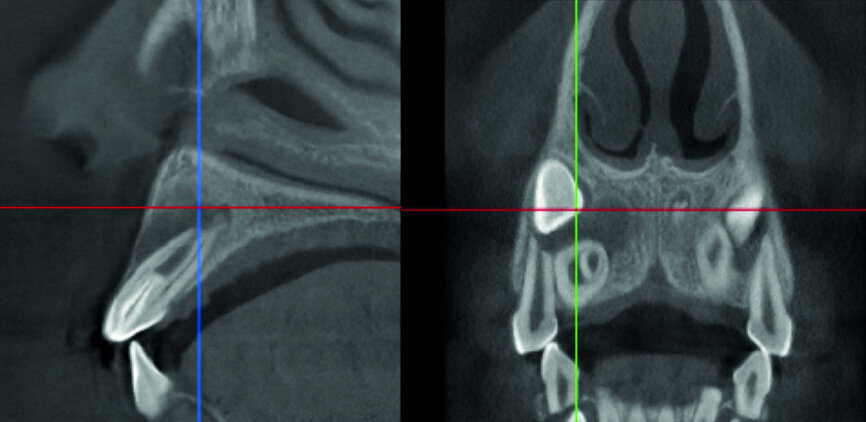

L’évaluation CBCT préopératoire est utile dans les cas nécessitant une approche chirurgicale, non seulement pour confirmer la présence d’une lésion, mais aussi pour planifier l’intervention et, en particulier, identifier le type d’incision chirurgicale à pratiquer, en fonction de la taille et de l’emplacement de la lésion en question (Photo : Dr Fabio Gorni)

Le cas avec lequel je souhaite commencer mon exposé clinique est un exemple parfait de la difficulté à définir l’origine des symptômes d’un patient, par l’examen d’une simple radiographie intraorale. Non seulement l’examen 2D ne permet pas d’établir avec certitude la présence d’une lésion, mais surtout, il est impossible d’en déterminer la taille, la morphologie et le type. Au contraire, une analyse de l’imagerie 3D offre une image claire de la situation clinique. Chez ce patient, les coupes coronales et sagittales révèlent la présence d’une importante lésion s’étendant de l’apex de la racine mésiale de cette molaire jusqu’à la zone de furcation, tandis que les coupes axiales nous permettent d’analyser précisément l’anatomie endodontique et, en particulier, la forme de la racine mésiale, qui apparaît fusionnée avec la racine palatine. Un panorama complet du cas peut donc guider le processus de décision et orienter le plan de traitement vers une modalité bien précise de traitement (Figs. 1–4).

L’évaluation CBCT préopératoire est utile dans les cas nécessitant une approche chirurgicale, non seulement pour confirmer la présence d’une lésion, mais aussi pour planifier l’intervention et, en particulier, identifier le type d’incision chirurgicale à pratiquer, en fonction de la taille et de l’emplacement de la lésion en question (Figs. 23–25). Le cas spécifique présenté dans cet article est caractéristique de cette situation. La radiographie intraorale n’a pas permis de déterminer l’étendue de la lésion, qui touche non seulement la région apicale de la prémolaire, mais aussi un segment édenté en distal. Cette région doit faire l’objet d’un traitement régénérateur, afin de garantir la cicatrisation appropriée de la zone, suivi par la mise en place d’une membrane. Une approche totalement différente de celle requise pour la chirurgie endodontique doit être utilisée pour protéger le lambeau. Les différentes étapes de l’intervention sont illustrées dans les images peropératoires (Figs. 26–28). L’examen CBCT réalisé 12 mois plus tard, confirme la cicatrisation complète de la lésion apicale et la parfaite intégration de la greffe (Figs. 29–31).